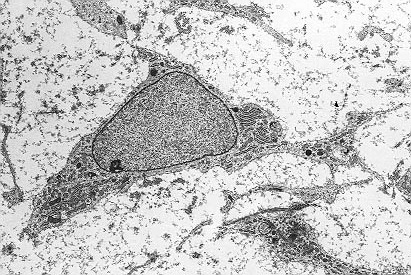

La artrosis es la degeneración del cartílago articular, que conduce al desarrollo de fisuras y erosiones y que provoca dolor e impotencia funcional. Cursa con inflamación por lo que los medicamentos antiinflamatorios están indicados en el tratamiento de esta enfermedad. Las lesiones focales pueden tratarse satisfactoriamente implantando condrocitos, pero en las lesiones difusas este tratamiento no está indicado. El cartílago articular tiene una capacidad regenerativa muy limitada, por lo que los tratamientos habituales son sintomáticos. La evolución de la calidad del cartílago articular puede seguirse por métodos avanzados de resonancia magnética.